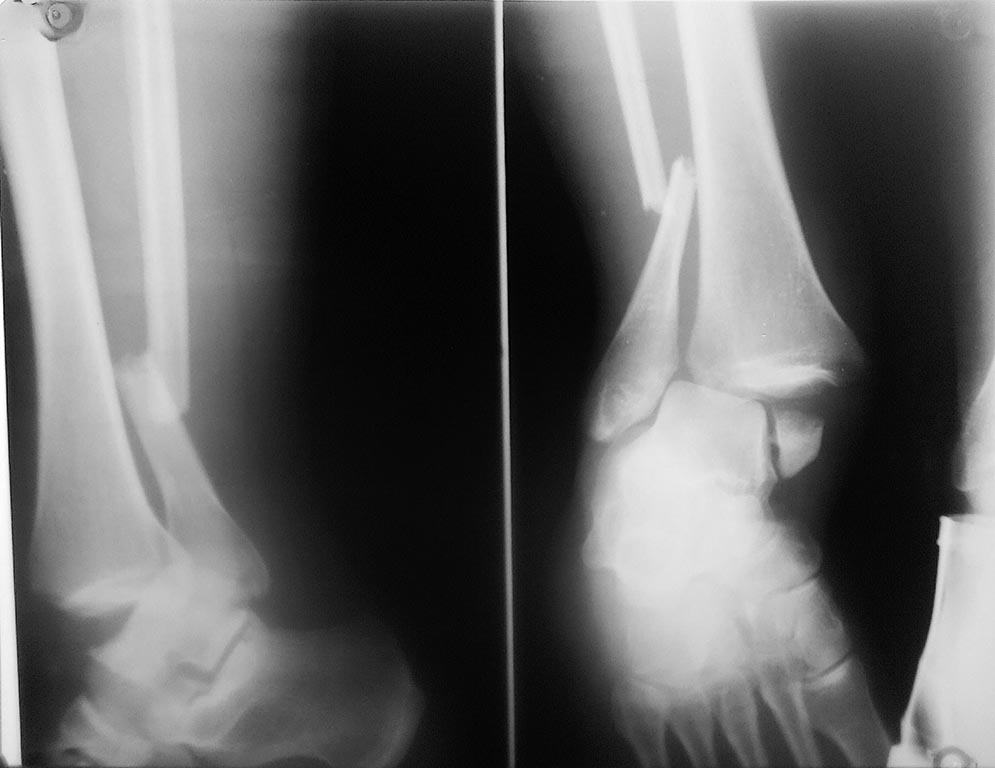

Уважаемые коллеги. Пациентка, 34 года получила травму в результате ДТП 06.08.2016. Перелом лодыжек 44С. Оперирована 12.08.2016.

На снимке 1 таран с подвывихом кпереди, немного. Массивность разрывов капсульно-связочных структур?

Уважаемые коллеги. Получается, что из-за углового смещения дистальный отломок м/берцовой кости не анатомично попал в вырезку ББК(в ДМБС)в следствие чего и наблюдается передний подвывих? Прошу прощения за качество снимков.

По моему мнению на снимке в Мортисе длина м/берцовой кости востановлена (субхондральные пластинки совпадают), единственное что неравномерность суставной щели(может из-за неправильной укладки?).